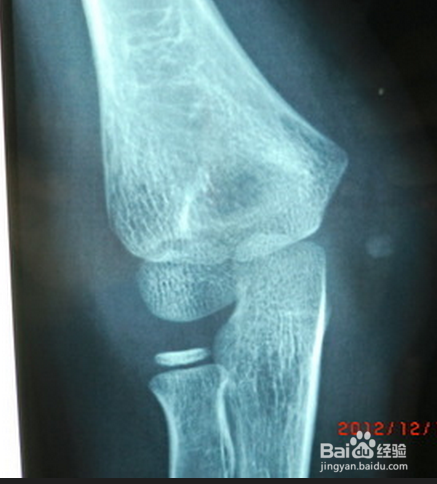

6、X线检查

通过做肘关节的X光片,可以明确诊断。同时X光片还可以对肘关节脱位进行分型并指导复位治疗。